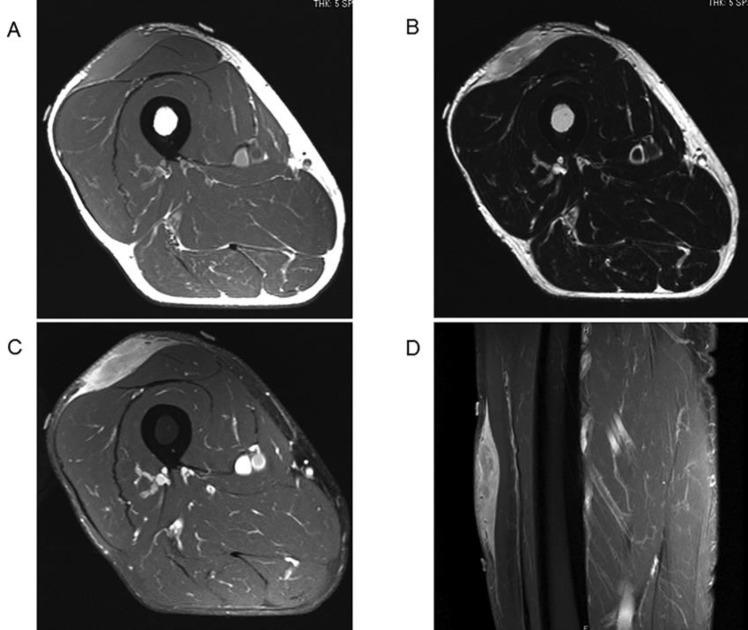

Spontaneous Regression of Myxofibrosarcoma of the Thigh after Open Biopsy.

Spontaneous regression of sarcoma is exceedingly rare. A 62-year-old male presented with myxofibrosarcoma of the thigh which regressed after open biopsy. Treatment strategy for this condition is not well-documented in the literature. In this report, we describe the case of a spontaneously regressed myxofibrosarcoma successfully treated by resection where the extent of the tumor was determined from the initial MRI. This case demonstrates that myxofibrosarcoma has the potential to regress spontaneously, and astute awareness of this phenomenon is necessary for appropriate management of this condition.